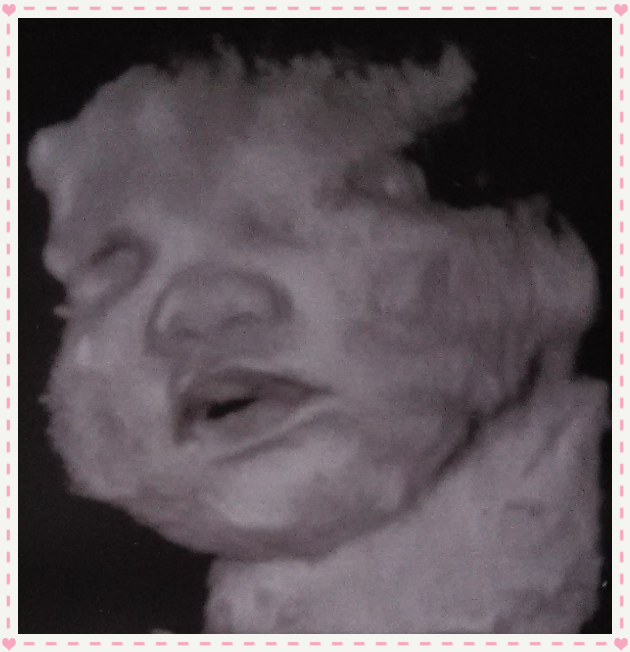

• I got a growth us because baby was measuring big & everything was good except her tummy. Turns out I have late GD. Did you get a 3hr glucose test? Also the us are known for being 1lb over or under & are not exact weight. But as far as you being further along if everything else is measuring on target except tummy maybe you just have a chubby baby. My us tech kept telling us theres nothing cuter than a chubby baby. Pic is of my chubby girl at 35.4wks estimated weight being 8lbs & tummy measuring a 42.3wk baby

• Awww look she is so cute and their little chubby cheeks are so kissable lol. I did do the 3 hour gluclose test and it was normal